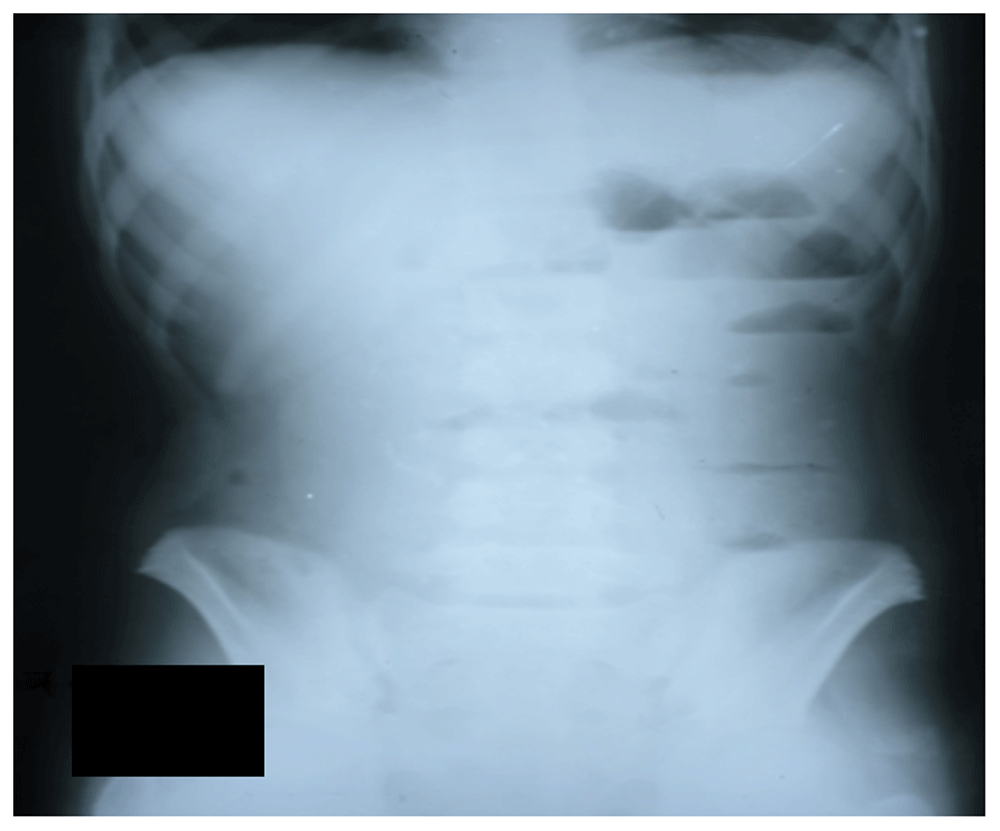

At the time of presentation in our hospital, the patient was vitally stable, pale-looking with a nasogastric tube placed in the right nostril. Her abdomen was soft, distended with centrally placed umbilicus and gut sounded sluggish on auscultation. Otherwise, she had no visceromegaly. The patient’s drain attached to the nasogastric tube collected 850ml greenish aspirates over 8 hours. Visual assessment of the aspirated fluids showed particles of ingested medicine. Basic laboratory workups, including complete blood count, electrolytes, and creatinine, were performed (Table 1). X-ray of the abdomen done at our hospital showed a deeply placed nasogastric tube with distended bowel loops (Figure 1 and Figure 2). The nasogastric tube was removed and the patient was kept on intravenous ceftriaxone (1 gram twice daily) and metronidazole (250mg every 8 hours for 3 days). Surgical consultation was reviewed and after 6 hours she was allowed liquids and foods orally, initially for liquids then after 8 hours solid food was given.

Figure 1. X-ray of the abdomen showing diffuse fecal loading.